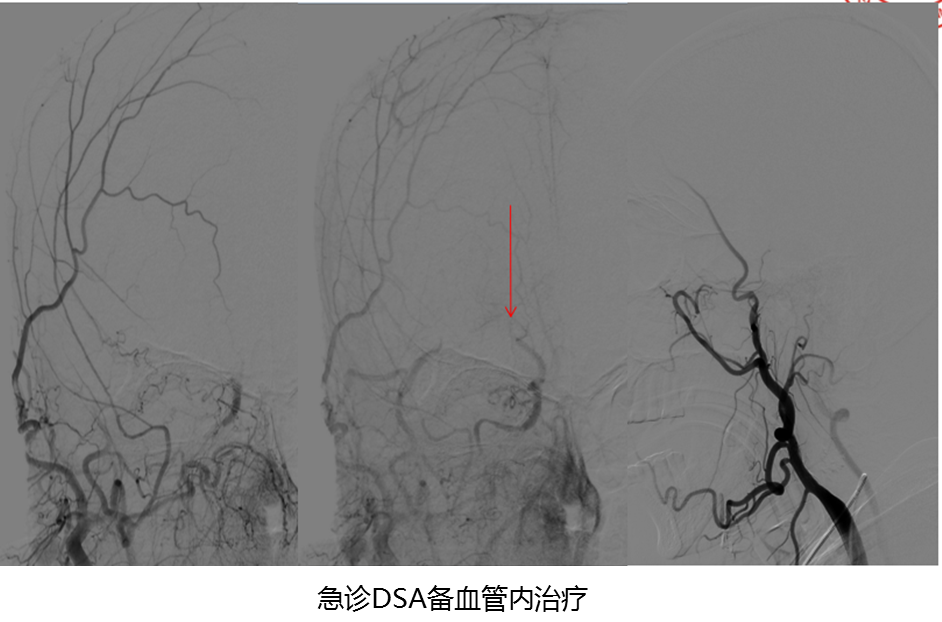

病历夹什么径技·第151期|串联营病历夹:京广连营_https://www.jmylbn.com_新闻资讯_第60张

结论:急诊MRI提示大脑右侧中动脉闭塞

病历夹什么径技·第151期|串联营病历夹:京广连营_https://www.jmylbn.com_新闻资讯_第61张

病历夹什么径技·第151期|串联营病历夹:京广连营_https://www.jmylbn.com_新闻资讯_第62张

病历夹什么径技·第151期|串联营病历夹:京广连营_https://www.jmylbn.com_新闻资讯_第63张

病历夹什么径技·第151期|串联营病历夹:京广连营_https://www.jmylbn.com_新闻资讯_第64张

<<滑动查看下一张图片>>

• 造影提示颈内起始部位闭塞,隐约有残端出现,大脑中动脉未显影,考虑大脑中动脉闭塞。

• 球囊扩张颈内起始部位,跟进中间管与Guiding后进行大脑中动脉取栓。

• 回撤导丝,大脑中动脉显影良好,术后继续抗血小板、补液。